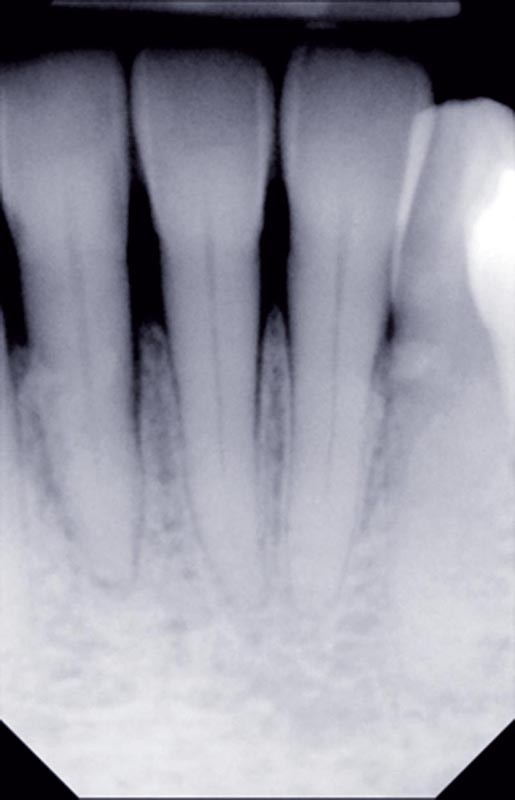

Au-delà du préjudice esthétique, il induit des forces importantes en direction vestibulaire sur les incisives mandibulaires. Ces incisives présentent une légère mobilité. La radio rétro-alvéolaire montre un élargissement desmodontal et une perte osseuse verticale sans cratérisation ni inflammation (fig. 3).